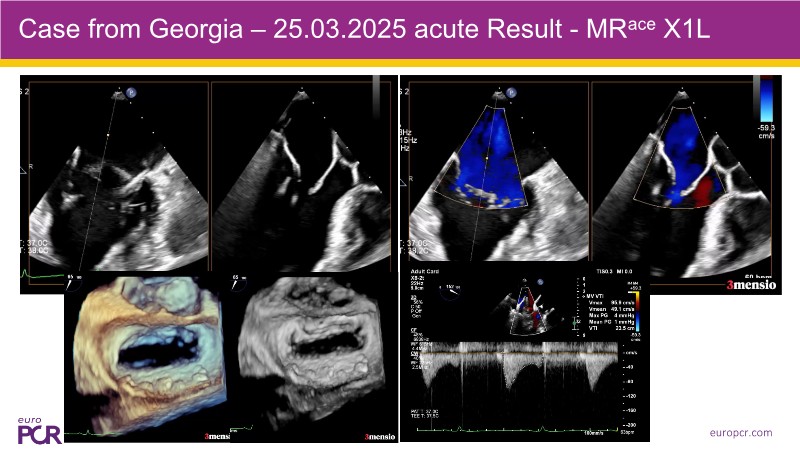

Active posterior leaflet replacement - A novel transcatheter approach for the treatment of primary and secondary mitral regurgitation

Find out more about an innovative transcatheter strategy for managing both primary and secondary mitral regurgitation in this EuroPCR 2025 session. Experts introduce the concept of active posterior leaflet replacement and present the Polares MRace device—a novel solution designed to address the limitations of current therapies. Gain insights into the device’s mechanism, watch two recorded cases demonstrating its use in clinical settings, and review the latest clinical and echocardiographic outcome data.

- To understand the device concept and its early clinical application in recent recorded cases